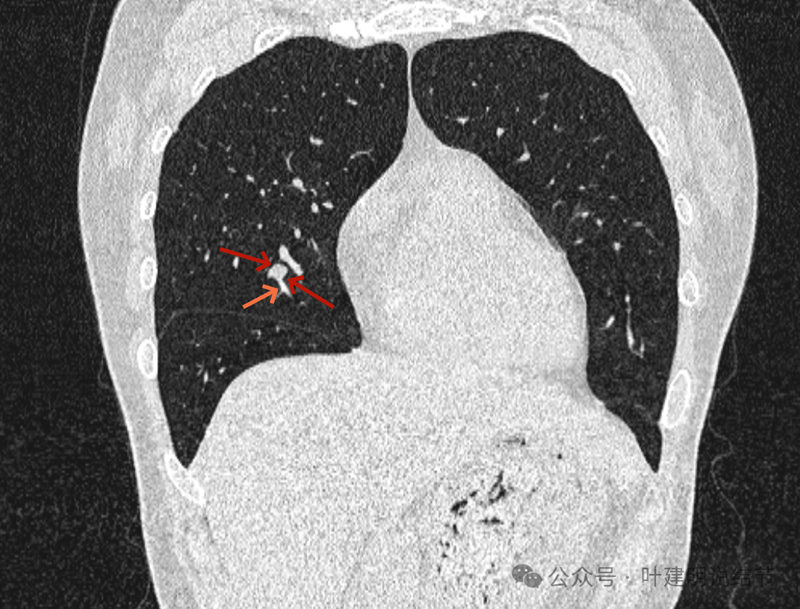

再看冠状位影像:

血管与病灶的关系,两者密度稍不同,天蓝色细箭头所指是分界线。

血管征明显。

血管围着病灶,病灶有膨胀性,表面欠平滑。

不而有膨胀性,血管贴着并被压迫。

边缘欠平滑,邻近血管间隙欠清晰。

血管贴着,结节膨胀。

也示血管与病灶的关系。

结节实性。